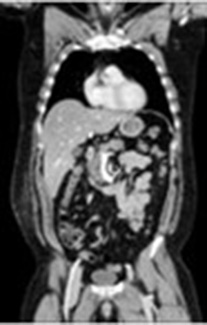

CT検査室

体の周囲360度からX線を照射し、体内を透過したX線量を解析し、画像にします。輪切りの画像だけでなく任意の断面の画像を作成でき、血管や骨などを立体的(3D)に表示することができます。

撮影時間を短縮、広範囲を撮影でき、息止めがある検査でも数秒と負担なく検査を受けられます。また体の大きさ、形に合わせてX線の量が自動で調整されるため被ばくを低減することができます。